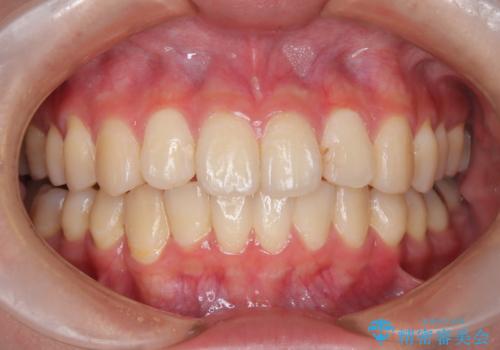

インビザラインによる矯正治療(非抜歯) 前歯の捻れとガタつきの改善

- 上下の前歯に捻れ(捻転)とガタつき(叢生)が見られます。

上の2番目の前歯の捻れに関しては、元々歯の大きさが小さい歯であるため、マウスピースにて力がかかりにくく、捻転の改善が一般的に難しくなりがちです。

下の犬歯に関しても捻れと傾き、ガタつきが大きく、歯根の長さも相まって移動の難易度が高くなりがちです。

インビザラインのそうした特色を踏まえた上で、それらをリカバーできるように治療方式の調整を十分に行い、治療を進めました。

マウスピース枚数 初回33枚 +追加22枚 +追加31枚

概ね2年で治療完了しました。

マウスピース矯正の特性として動かすのが難しい歯を含むケースでしたが、当院独自の工夫を随所に盛り込み、狙い通りの治療結果が得られました。